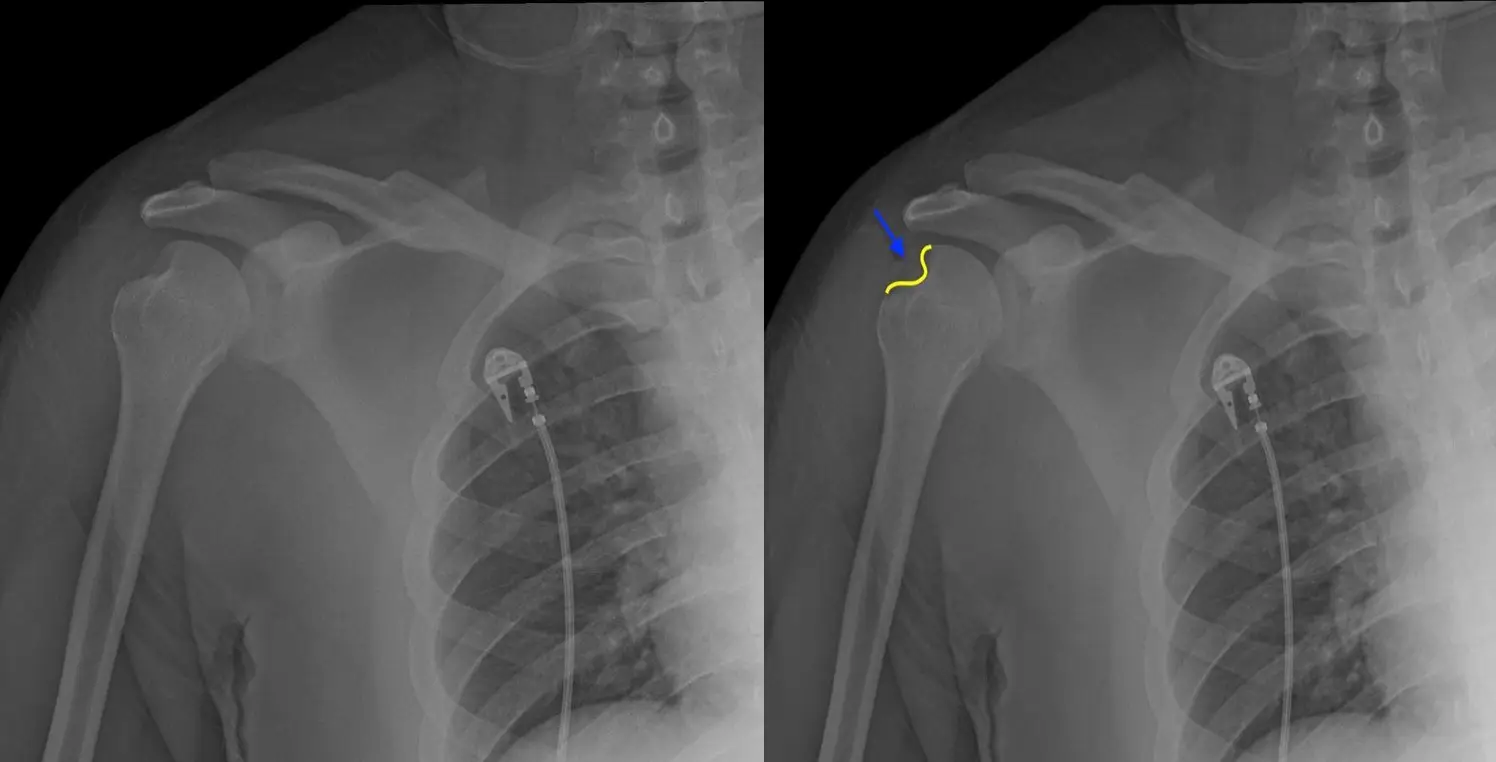

Hill Sachs lezyonu, kol kemiği (humerus) başının posterolateral kısmında kortikal çöküntü oluşması ile karakterize bir omuz yaralanmasıdır. Bu durum, genellikle anterior omuz çıkıkları sırasında meydana gelir. Özellikle humerus başı, glenoidin anteroinferior kenarına şiddetli bir şekilde çarptığında, kemikte kalıcı çöküntü oluşur.

Bu lezyon genellikle omuzun içe dönme hareketi sırasında daha belirgin hale gelir ve doğru şekilde teşhis edilmesi önemlidir. Bilgisayarlı tomografi (BT) veya MR görüntüleme ile kolun hareketi sırasında eklem yüzeyleri detaylı şekilde incelenebilir.